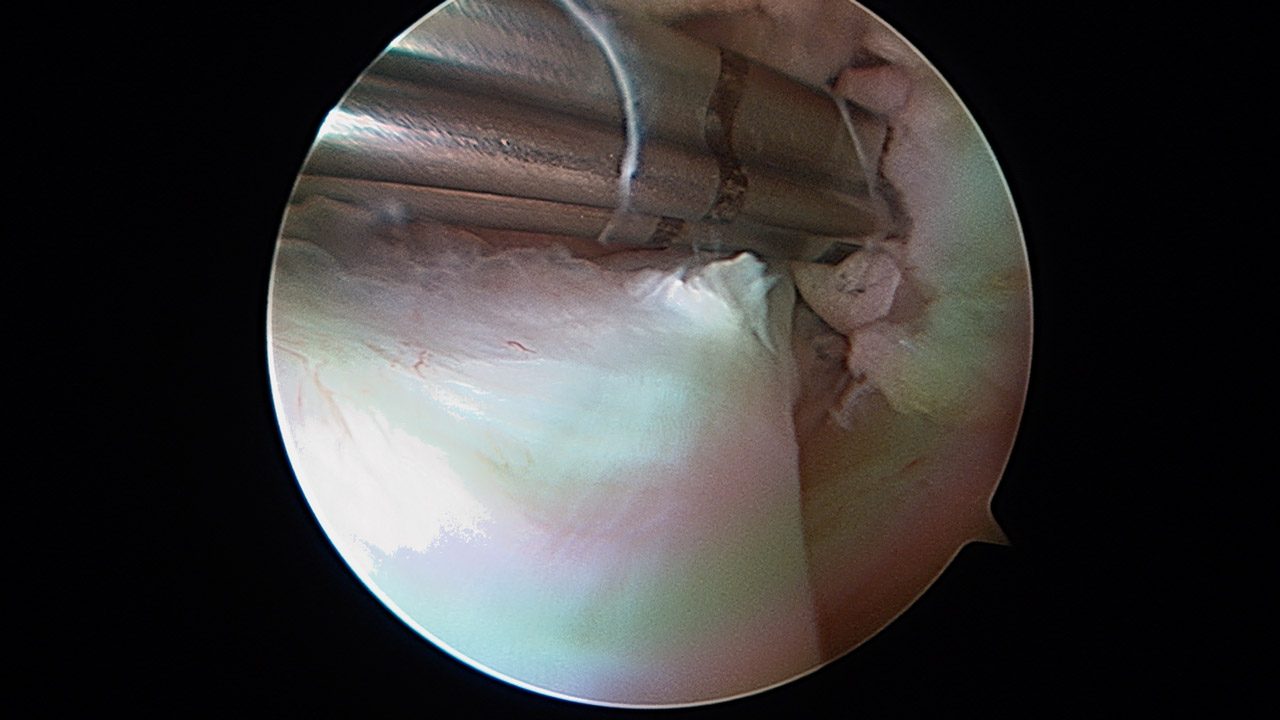

Paso 5: injerto

Para realizar la cirugía se usa un aloinjerto de tibial anterior, con una longitud de 10 cm y un grosor de 7 mm. Se introduce el injerto en el húmero fijándolo con un tornillo interferencial de 7 × 23 (Stryker, Kalamazoo, Mi) (Figura 9). Posteriormente, a través del split, se introduce en el orificio glenoideo, con fijación interferencial 7 × 23 (Stryker, Kalamazoo, Mi) (Figura 10). El injerto reproduce el LGHI, con dirección superior a través del subescapular, y se fija a 45° de rotación externa y 45° de abducción (Figura 11).